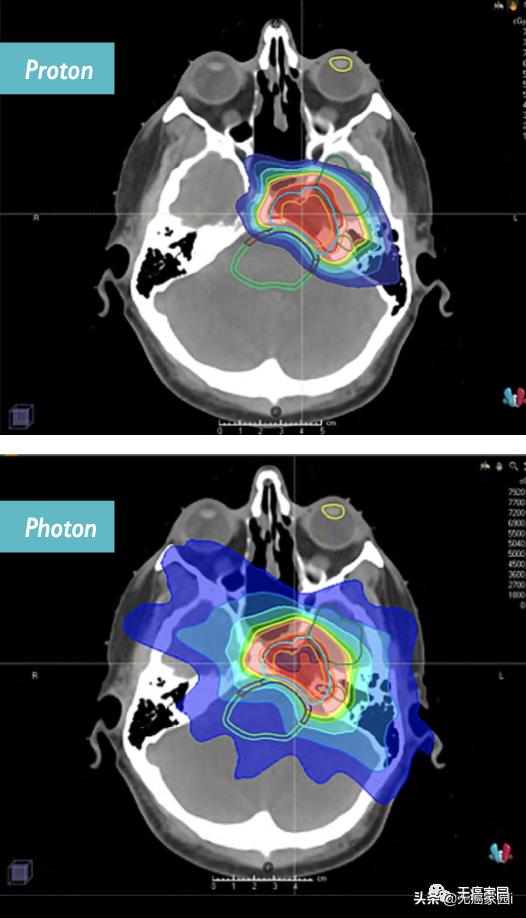

左图显示头颈癌的质子束治疗计划;右图显示X射线传统治疗方式

不得不说,头颈癌的治疗非常困难又复杂,即使上图中显示的两例患者的舌前部的风险为零,但是IMRT提供的低剂量,这些低剂量足以引起口腔大疼痛,并导致脱发;而使用质子治疗的患者则做到了零剂量,疾病风险为零。

IMRT 在头颈癌的放射治疗过程中给予广泛剂量的辐射

图片显示了这种辐射对没有患癌症风险的区域的影响,这是对正常组织的有害辐射